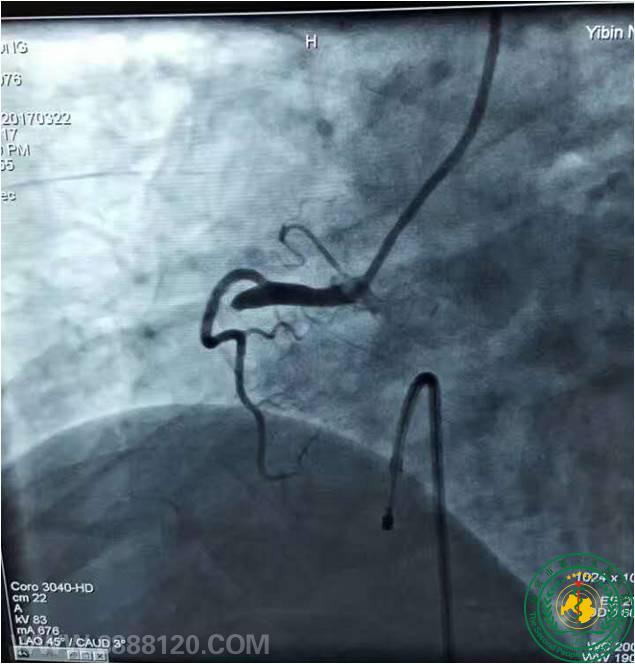

宜宾市第二人民医院 图文